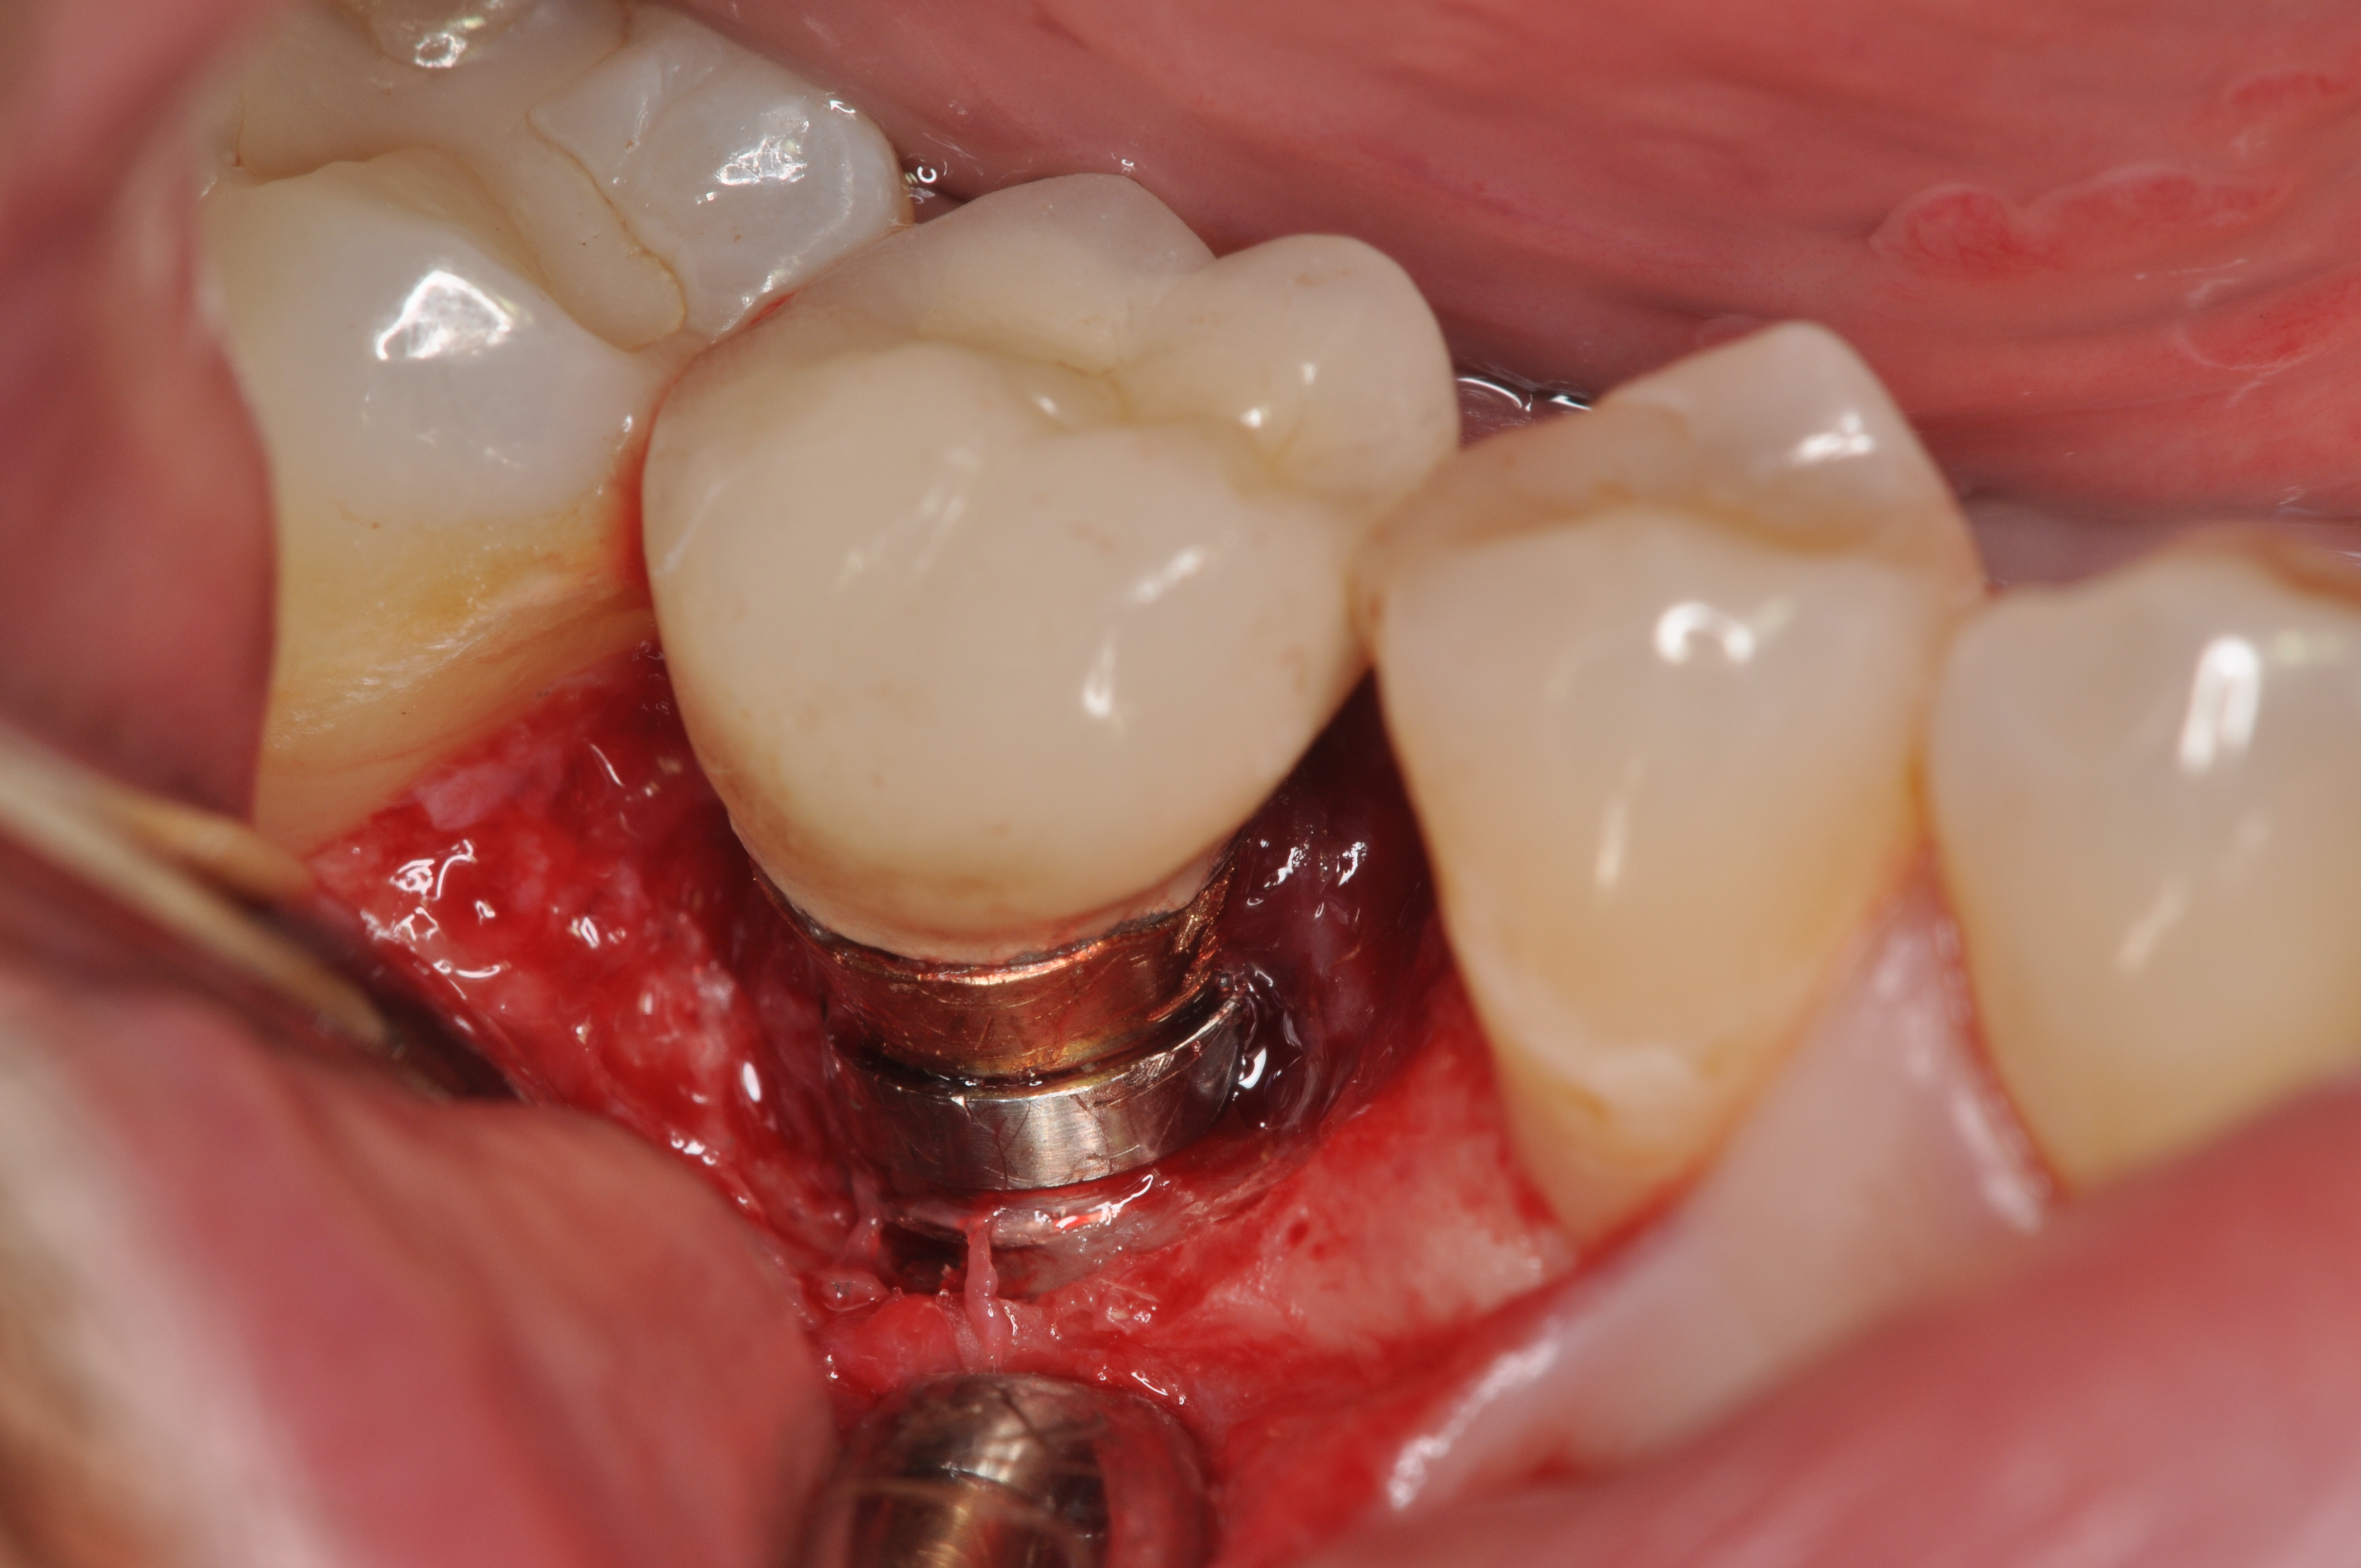

Fig 8. Loss of restoration and subsequent tissue overgrowth from broken abutment screw as shown in the radiograph (Fig 9).

Figure 8